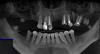

Olga NSK Опубликовано 9 августа, 2013 Поделиться Опубликовано 9 августа, 2013 Здравствуйте!Всю жизнь боялась стоматологического лечения + ужасная наследственность, результат видно на снимке. Единичные вылазки были, но довести дело до конца не удавалось ни разу - саботировала и пропадала. Но после курса психотерапии (не по поводу конкретно стоматологии, а вообще) таки решилась. Записалась на три консультации в разные клиники, жду будущей недели.На 11 и 23 стоял мост, закрывая отсутствующие 21 и 22, сейчас сломан и не функционален, исключительно декор, чинить его не хочу, а хочу: п.1 Санация. Скорее всего, синус-лифтинг. Имплантировать 21 и 22, на 11, 23, 24, 45 - коронки. 27, скорее всего, предложат удалять - над ним в десне свищ и он сильно наклонился и съехал, занимая место почти отсутствующих 26 и 26. Поставить на место отстутствующих жевательных зубов нейлоновые съёмные на время накопления средств на следующий пункт. п.2 Имплантировать 25, 26, 27 и 36, 37. Сделать паузу на накопление средств на п.3, оставив нейлон на правой стороне. п.3 Имплантировать 14, 15, 16, 17 и 46, 47. Вопрос в том - делают ли так вообще? Если делают, то верен ли мой план протезировать разом не по челюстям (сначала нижнюю, потом верхнюю), а по сторонам? Съёмные в плане изчезновения кости и дёсен мне не страшны, т.к. жевательные отсутствуют давно.Заранее спасибо Ссылка на комментарий

IvanK Опубликовано 10 августа, 2013 Поделиться Опубликовано 10 августа, 2013 ЗдравствуйтеУдаление корня 17, корня 25, 26?, 27,38,48Синус лифтинг справа, слева? далее имплантацияНижняя челюсть: имплантация Хирургические этапы Вы можете разбить, протезировать нужно все вместе.Мне не нравятся лечение с ношением съемного протеза Съёмные в плане изчезновения кости и дёсен мне не страшны, т.к. жевательные отсутствуют давно. очень возможно, что потребуется работа по "наращиванию" костной ткани + работа с мягкими тканями Ссылка на комментарий